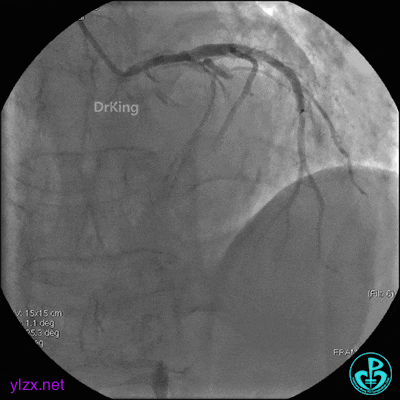

4 急诊冠脉造影

左主干轻度狭窄,左主干到前降支近端钙化影明显。前降支开口严重狭窄,近端闭塞。粗大回旋支轻度狭窄。

右冠脉无严重狭窄,右冠脉没有给前降支提供逆向供血。